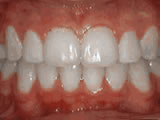

Spacing of teeth

spacing of teeth beforeBefore

spacing of teeth afterAfter

Patient was bothered by the spaces between his teeth. Braces closed the spaces and gave him an ideal bite in 24 months. Special glued-in retainers help keep the spaces closed.